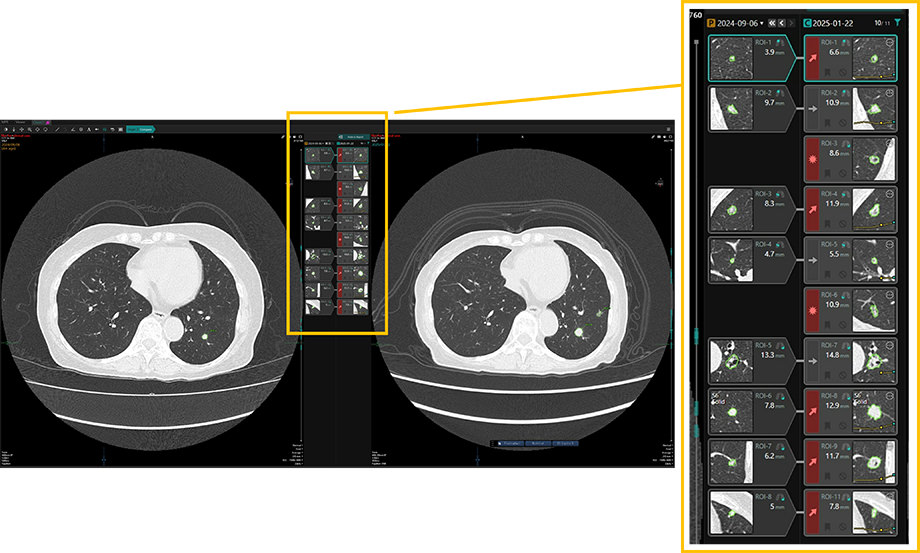

そこで、京都大学とキヤノンでは、骨領域の読影だけでなく、肺の読影を支援するシステムの研究にも取り組み、実現したのが「関心領域比較機能」です。胸部CTの撮影データから、AI技術を活用した解析処理により肺野領域の組織における特徴的な関心領域を抽出し、そのサイズと体積を測定する既存の技術に、キヤノン独自の高度な位置合わせ技術を組み合わせました。これにより、過去と現在の画像を並べて表示し、抽出された肺の関心領域を経時的に紐づけ、サイズの変化などを一目で比較することができるようになりました。

高度な位置合わせにより現在の検査画像と過去の検査画像の関心領域を自動的にペアリングし、サイズの変化を分かりやすく表示する「関心領域比較機能」